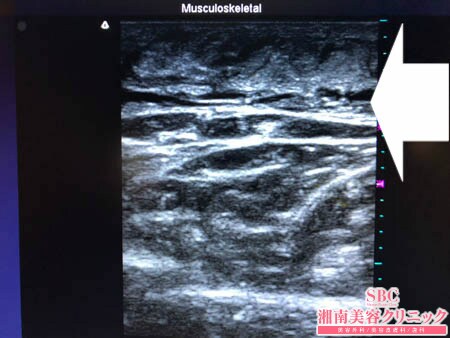

No.205646【脂肪吸引】【動画あり】湘南美容外科全ドクターの脂肪吸引最高責任者である竹田先生による脂肪吸引のフォトギャラリー!他院の再手術!スタッフさんの太ももを再度綺麗に根こそぐ!術中3Dタッチビュー・左太もも前面

では術中の模様を紹介しましょう。

まずは取り残された皮下脂肪を

徹底的に根こそぎました!!

そして可能な限り滑らかに根こそぎました!!